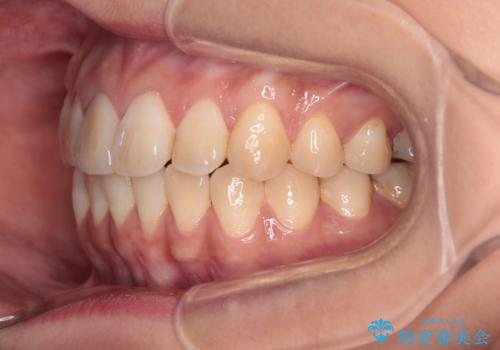

舌の突出癖による開咬と前歯の突出 インビザライン矯正治療

- 上下前歯の非接触と叢生を気にして来院された患者様です。

開咬の改善はインビザラインの最も得意とするところであるため、インビザラインを用いて矯正治療を行うこととしました。

治療開始直後に上顎前歯に激しい痛みが発現し、矯正治療を休んだり、マウスピースの装着時間を短くしたりと工夫をしましたが、残念ながら治療途中で失活していることが分かりました。

矯正治療の途中で前歯の根管治療とオールセラミッククラウンによる補綴治療を行い、その後インビザライン1セットを用いて細かい部分を仕上げました。